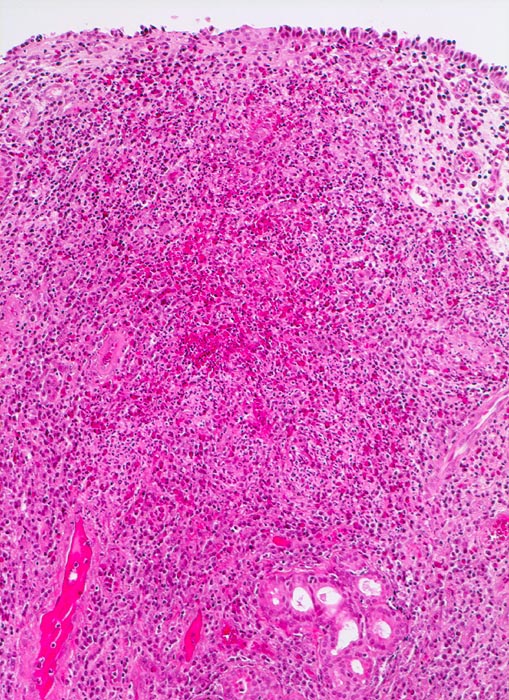

chronische polypöse Rhinitis

Nasenschleimhaut

Einzelne seromuköse Schleimdrüsen und sehr dichtes gemischtes Entzündungsinfiltrat im vermehrten Stroma.

Patient mit nicht allergischem Asthma klagt über chronische dumpfe Kopfschmerzen und behinderte Nasenatmung. Bei der anterioren Rhinoskopie sind multiple Polypen der Nasenschleimhaut im Bereich des mittleren Meatus sichtbar.

Histologie

100